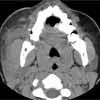

Facial CT scan as shown.

Facial CT revealed a 3-mm calcification in the distal portion of the parotid duct, diffuse enlargement of the parotid gland, and regional lymph node enlargement. After a dose of ampicillin/sulbactam, the patient was discharged with pain medication and a prescription for oral antibiotics. She was advised to apply warm compresses and to suck on sialogogues (sour candy). Follow-up with an otolaryngologist in 7 days was also recommended.